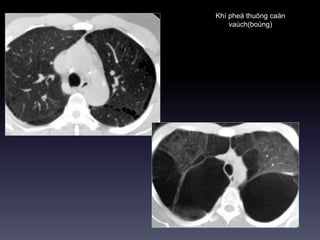

Congenital Lobar Emphysema

Khí thuõng trung taâm tieåu

thuyø

Khí pheá thuõng caän

vaùch(boùng)